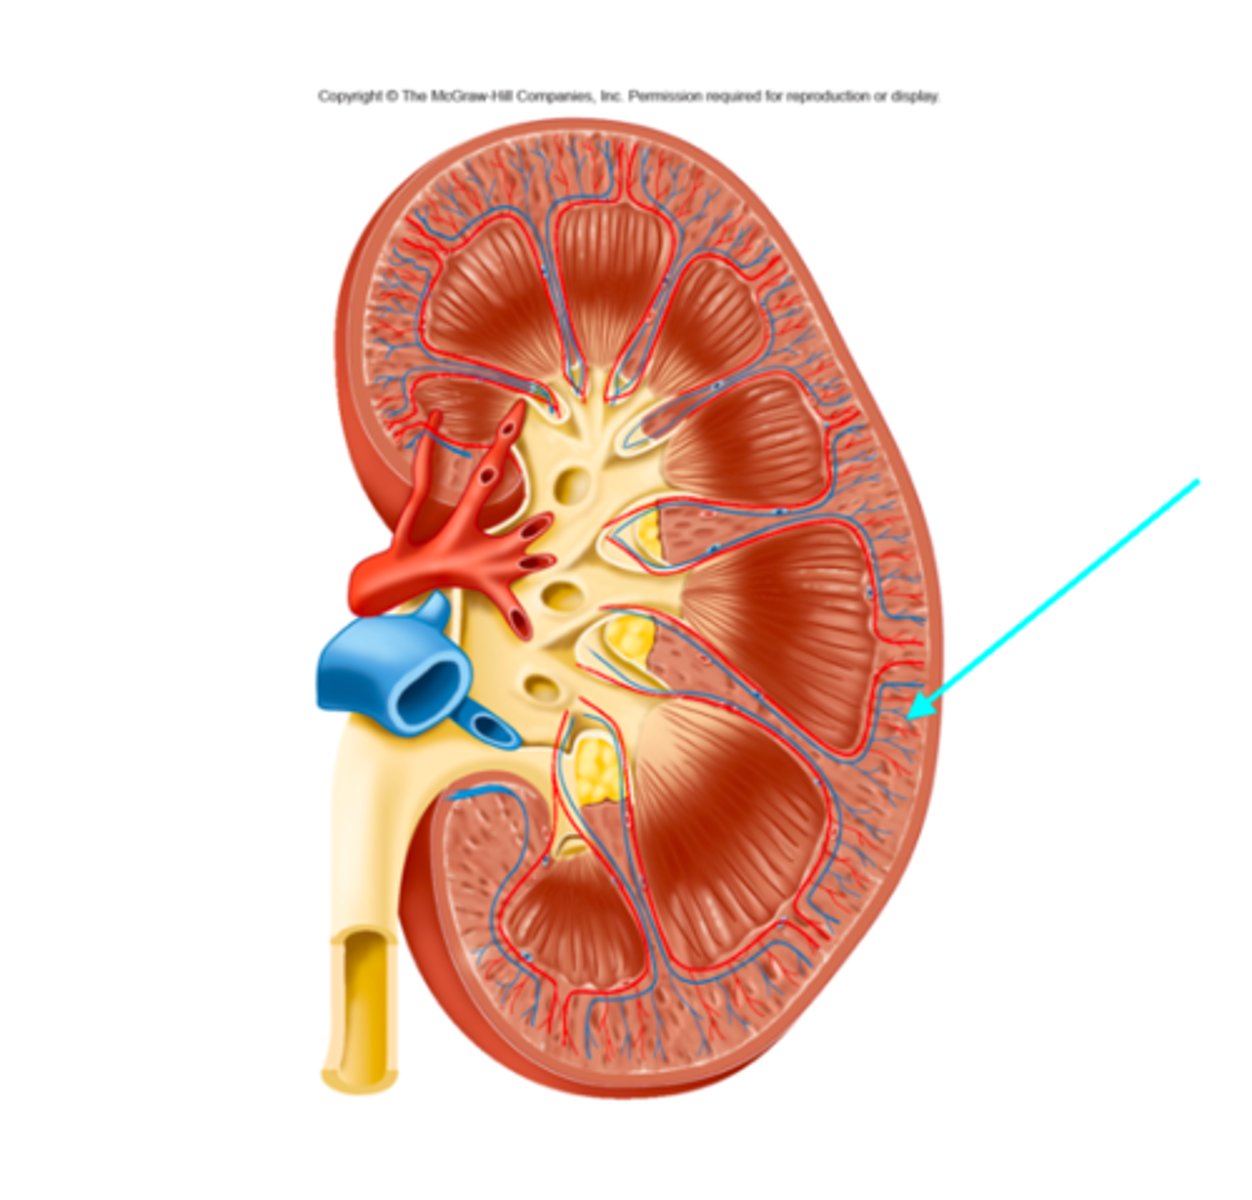

What structure of the kidneys is the blue arrow pointing at?

Juxtamedullary nephron

What structure of the kidneys is the blue arrow pointing at?